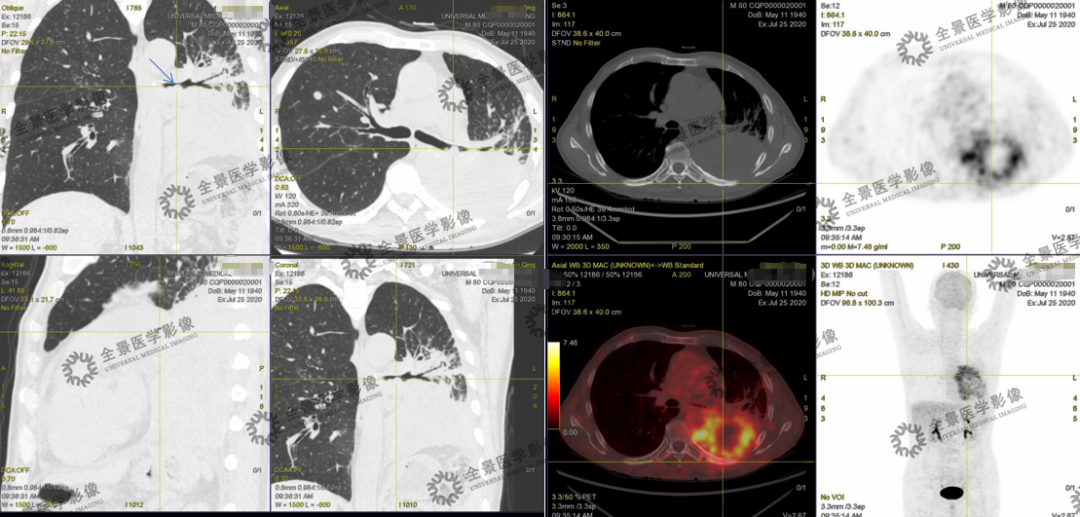

(1)临床以感染性病变治疗后无效——病理肺癌

(2)肺癌(N、M分期)

(3)肺癌治疗后复——有无复发或是转移

病例说明18F-FDG对肺癌N分期灵敏度高,可以发现微小淋巴结转移灶,减少漏诊率,对某些部位其他影像检查易漏诊淋巴结转移灶敏感(锁骨下窝、内乳动脉旁、心膈角区、膈脚间隙、肋间隙、肋间间隙)。对肺癌M分期灵敏度高,特别是骨转移早期,其他影像学,比如CT/MR没有异常密度或是异常信号,PET/CT可发现异常代谢增高,对肺癌正确分期提供依据。